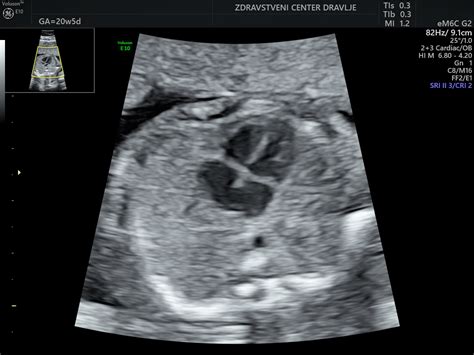

4. Mesec nosečnosti (približno 13.-16. teden): V četrtem mesecu je otrok velik med 15 in 17 centimetri in tehta približno 200 gramov. Začne razvijati reflekse, kot so sesanje in požiranje. Lahko že sesa palec in mežika. Na dlaneh in podplatih se tvorijo znojnice. Prstki na rokah in nogah so že oblikovani in imajo svoje prstne odtise. V tem času je možno z ultrazvokom določiti spol otroka. V 13. tednu plod meri približno 7 cm in tehta približno 20 gramov. Opazni so dihalni gibi, plod požira plodovnico in izloča urin. Koža je poraščena z mehkimi lanugo dlačicami. V 15. tednu plod meri približno 10 cm in tehta približno 70 g. Lahko že sesa svoj palec. Kosti skeleta se krepijo, razvoj mišic se nadaljuje. Oči so zaprte, vendar postanejo dovzetne za svetlobo, razvija se sluh. Od 16. tedna dalje je možna amniocenteza. Gibi okončin so vse bolj usklajeni.

V četrtem mesecu nosečnosti se telo matere še naprej prilagaja rasti in razvoju otroka. V 13. tednu plod meri približno 7 cm in tehta okoli 20 gramov. Na ultrazvočnem pregledu so že opazni dihalni gibi, plod požira plodovnico in izloča urin. Njegova koža je poraščena z mehkimi lanugo dlačicami, ki bodo izginile pred porodom. Do 16. tedna plod meri približno 10 cm in tehta okoli 70 gramov. Kosti skeleta se krepijo, razvoj mišic se nadaljuje, oči pa so zaprte, a že dovzetne za svetlobo, medtem ko se razvija sluh. V tem obdobju se lahko pojavijo tudi prvi znaki, da bo mama kmalu občutila otrokove gibe.